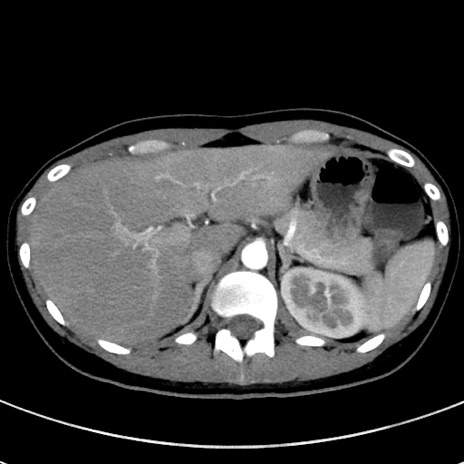

症例17(横断像)

【症例】20歳代女性

【主訴】嘔吐、下腹部痛

【現病歴】昨日夕食後に嘔吐し下腹部痛が出現。本日になっても嘔吐持続し改善しないため来院。

【身体所見】意識清明、BT 37.2℃、BP 108/67mmHg、腹部:平坦、やや硬、下腹部正中から右にかけて圧痛あり、反跳痛軽度あり、tapping pain(+)。

【データ】WBC 13600、CRP 14.94